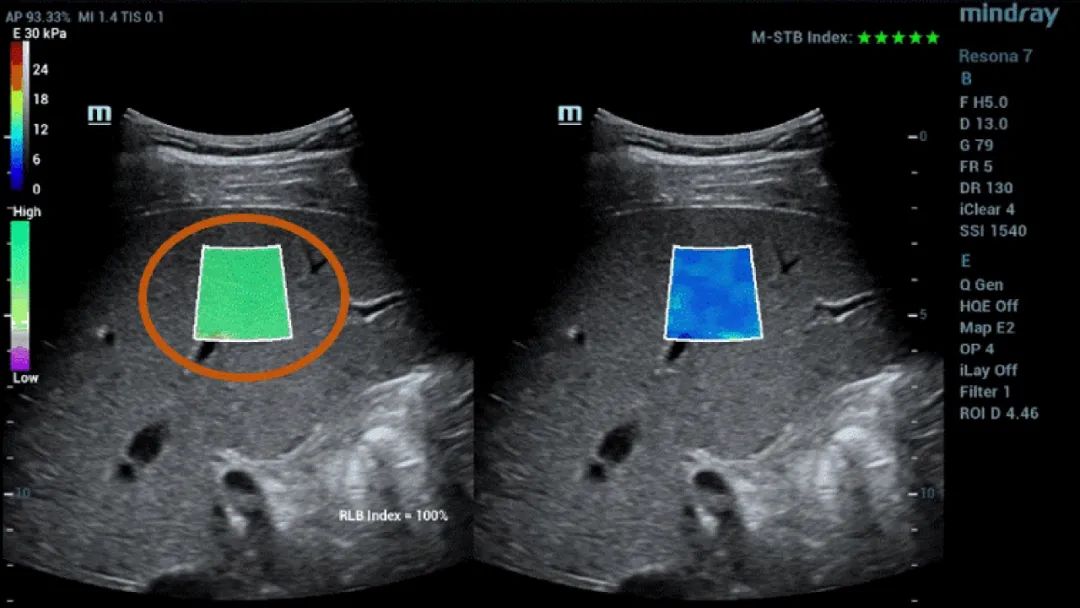

Şekil 1 (devamı): (e) 2D SWE (STE; Mindray, Shenzhen, Çin) ile elde edilen görüntüler. İki kalite kriteri sağlanmıştır: Yıldızlarla gösterilen (en yüksek kararlılık beş yeşil yıldızla gösterilmiştir) hareket kararlılığı (M-STB) endeksi ve mordan yeşile giden (İkincisi en yüksek güvenilirliği gösterir.) güvenilirlik (RLB) haritası. Yıldızlar, edinim sırasında hareketin bir göstergesidir. Dört yıldızdan az olduğunda, edinim sırasında önemli hareket vardır ve bu çerçeve karaciğer sertliği ölçümü için kullanılmamalıdır. (f) Elde edilen görüntüler

Ayrıca Mindray'in Sound Touch Elastography (STE) teknolojisi, 2D Shearvawe elastografi ile elde edilen ölçümler için hareket kararlılığı (M-STB) indeksi, güvenilirlik (RLB) haritası, güvenilirlik (RLB) indeksi vb. ile operatörlerin görüntü elde etme standartlarını onaylamasına yardımcı olan güçlü kalite veya güven faktörleri sağlar.

RLB haritası, mordan yeşile giden STE görüntülerinin güvenilirliğini gösterir. İkincisi en yüksek güvenilirliği belirtir. RLB Endeksi ≧%90 olduğunda, görüntü güvenilirdir.